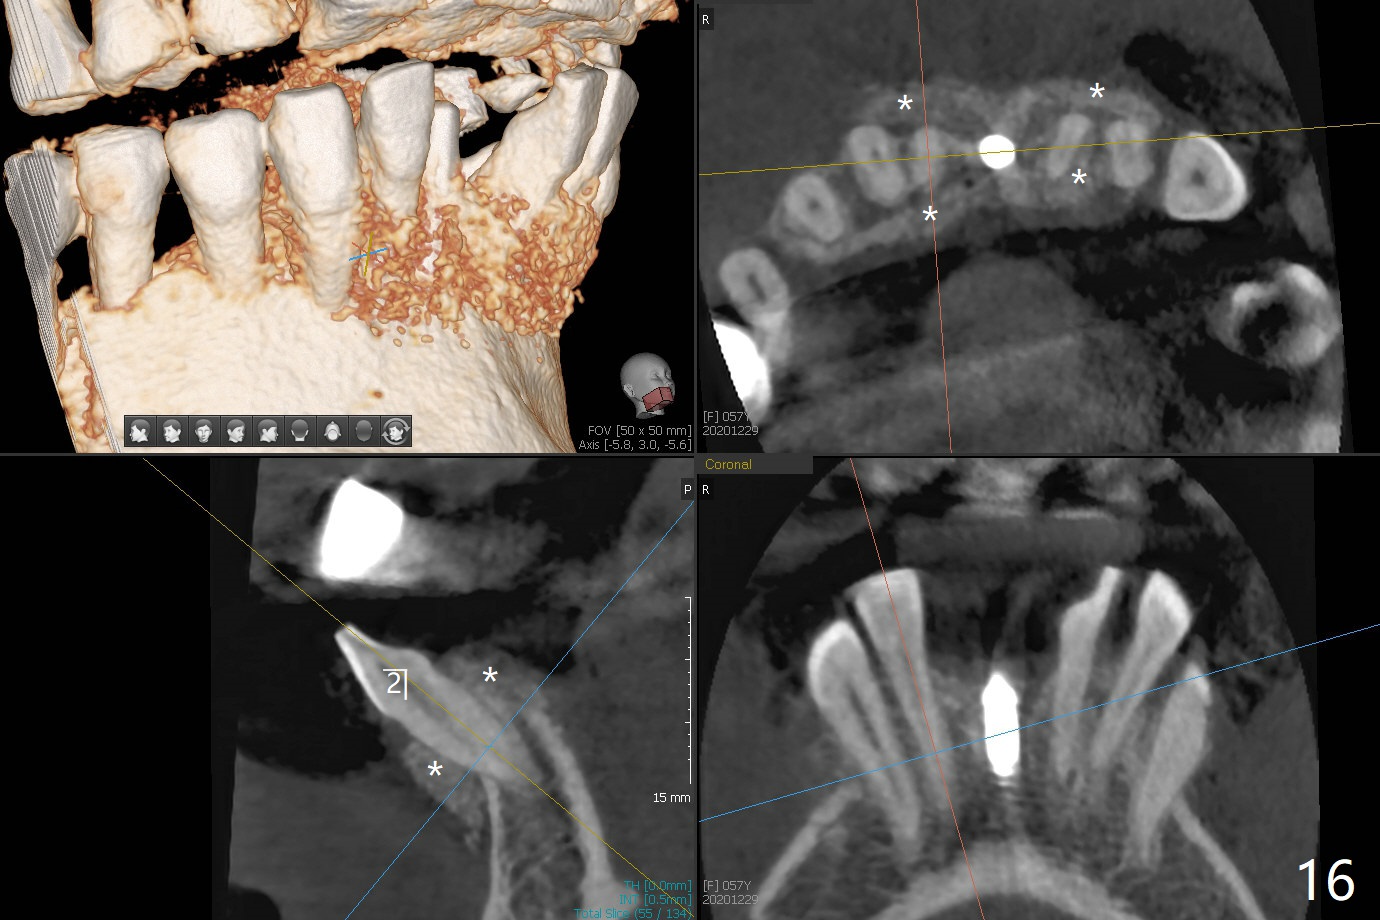

56岁女十分恐惧治疗,缺失右下1,其余切牙由于骨质吸收颊侧移位(图一:1,2),但是她不愿意拔除,同意右下1种植,牙周骨手术,植骨;植体整合后作为支抗,矫正移位下门牙。为了防止忘记舌侧瓣分离,先做舌侧切口(图二),然后颊侧瓣松弛分离(图三),包括使用前牙隧道刀(图四)切断颊侧骨膜,松弛到颊侧瓣能向舌侧牵拉3-4毫米(图五),舌侧瓣骨膜下广泛,深部分离(好像不能切断骨膜,图六),放置导板,磨平狭窄的牙槽嵴(图七:O(osteotomy)),植入2.5x12(4)毫米一段式植体(图八:故意舌侧植入,以便以后矫正),在颊侧骨板打多个出血洞(图八:箭头),然后把在平的器皿上形成的粘性骨板(sticky bone,图九),放置于植体和移位切牙周围(图十),接着使用消毒过的橡皮障punch(图十一(纸头相当于PRF膜;事先给助手示范))在三个PRF膜(图十二)打洞,套在植体和门牙上(图十三: 箭头),防止膜(图十四)和骨块(图十五,十六:*)移位,最后还必须使用最原始方法牙周敷料保护伤口(图十七)。术后9天,舌侧牙周敷料脱落,伤口稍微裂开(图十八)。术后18天撤除敷料,伤口裂开处有新鲜肉芽组织生长(图十九(*:下面是填入的骨粉,将是增宽的牙槽嵴(如果你是乐观主义者)),二十)。病人十分感激我们帮助她度过难关。她的确有sleep apnea,否定tongue thrust。术后三个月植体周围没有明显骨质吸收(图二十一至二十三),左下1,2轻度反合(图二十四),植体周围软组织健康(图二十五),5-5安置矫正器(图二十六,二十七,12 niti)。一周后下切牙向舌侧移动(图二十八),左下1,2反合纠正(图二十九)。再一周变化不大(图三十),植牙圈有些松动,两周后将重做临时牙冠,槽往舌侧移动。结果病人提前回来,植牙槽舌侧移位。一周后右下2不适(图三十一),尝试近中牵引(图三十二)。